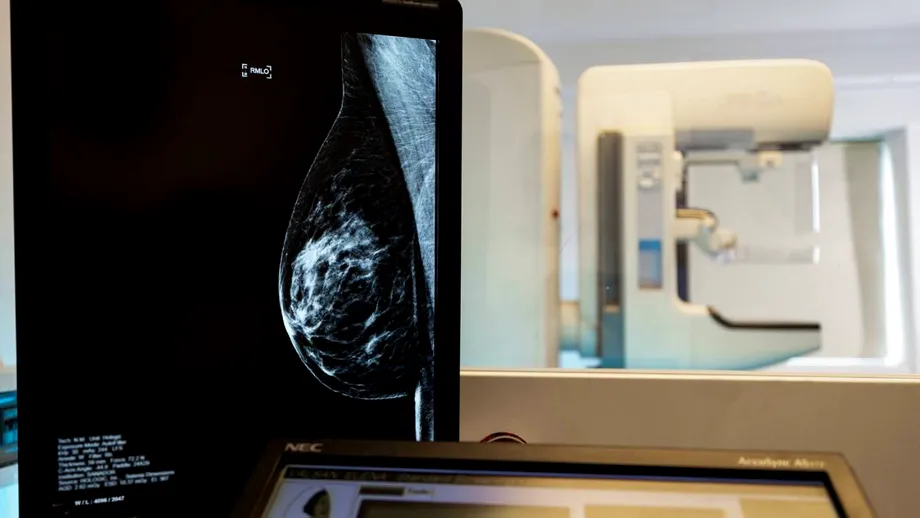

Cancerul de sân: de la diagnostic precoce la tratamente personalizate

Potrivit Dr. Florentina Bratu, medic primar oncologie medicală, Centrul Oncologic SANADOR, apariția cancerului de sân nu are o singură cauză, ci este rezultatul unei interacțiuni complexe între factorii genetici și cei de mediu.